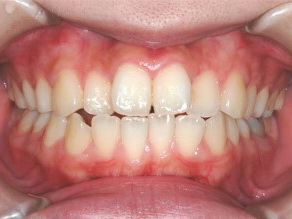

永久歯に交換するためのスペース不足による前歯のガタガタで、取り外しができる拡大床にて上下顎の幅を拡大した後、上顎の前歯をマルチブラケット装置で並べました。治療の期間は1年9か月でした。

初診時

終了時